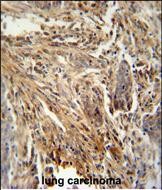

IHC 1/100-1/500 Human,Mouse,Rat

ImmunogenThis CSF2 antibody is generated from rabbits immunized with a KLH conjugated synthetic peptide between 59-85 amino acids from the Central region of human CSF2.